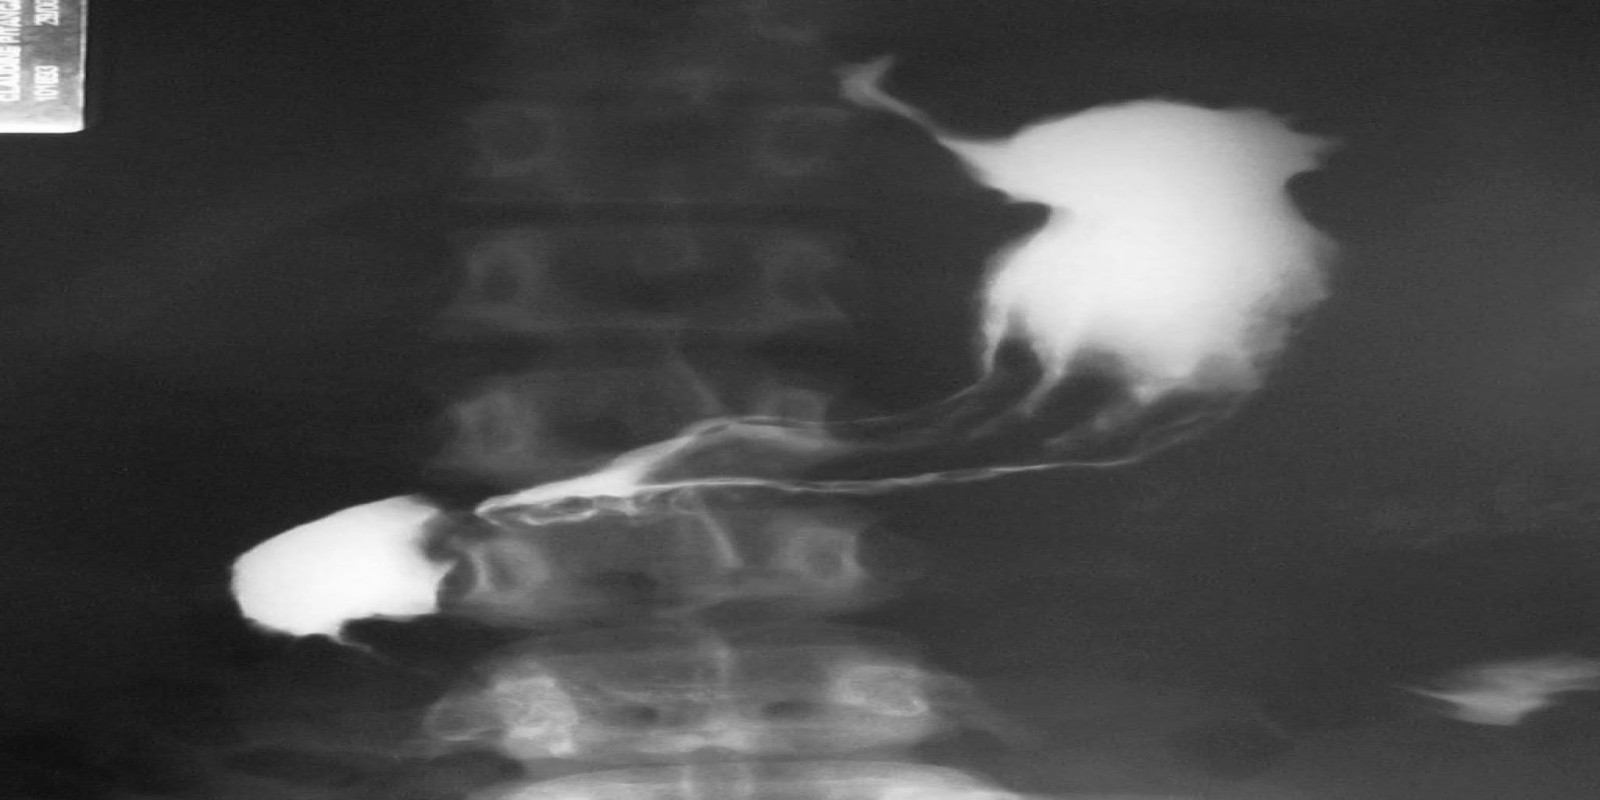

Caso Código 041A de Câncer Gástrico

Cod.: 041A